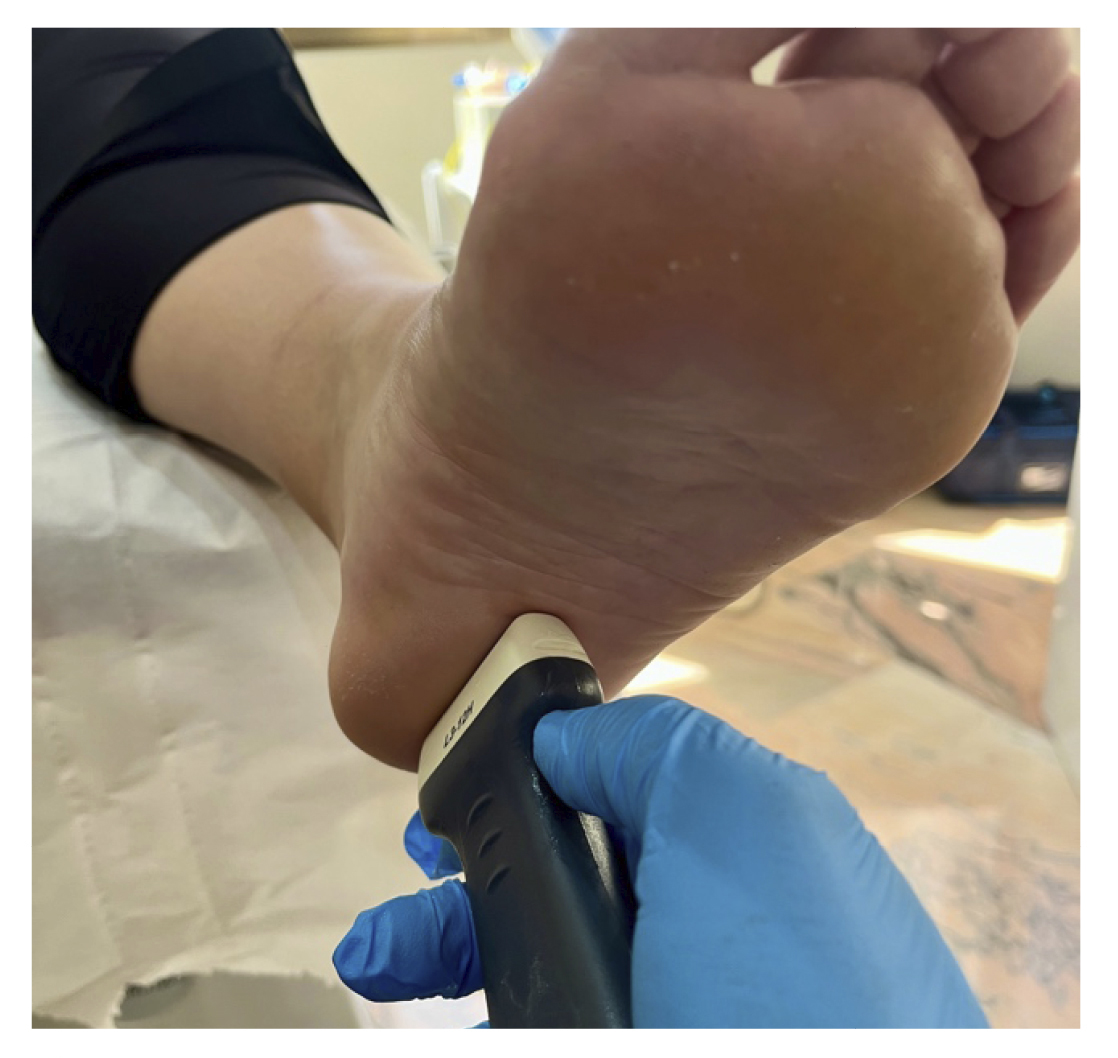

A todos los pacientes se les realizó una evaluación clínica y una evaluación ecográfica. La evaluación clínica se basó en una escala analógica visual (EVA) (13) (0-10) y el índice de función del pie (FFI) (14,15), que evalúa la función en una escala de 0 a 100. También se clasificó a los sujetos como sedentarios, activos o deportistas en función a su actividad física diaria, así como si era la primera vez que aparecía la enfermedad, era una recidiva o era crónica(16). También se evaluó el sexo, el peso y la talla, la presencia de vascularización en la fascia plantar visualizada con ecografía en el momento de la evaluación inicial y la forma biconvexa(17) o aplanada de la fascia plantar (Figura 1).

Figura 1. Fascia plantar con morfología normal a la izquierda y fascia plantar con morfología biconvexa a la derecha.

El diagnóstico se estableció en base a los síntomas y se confirmó mediante ecografía con equipo de alta resolución (Alpinion Ecube 9, ALPINION MEDICAL SYSTEMS Co., Ltd., República de Korea) con transductor lineal de 6 a 12 MHz (Figuras 2 y 3).

Figura 2. Investigador con la sonda lineal para la medición del grosor de la fascia plantar.